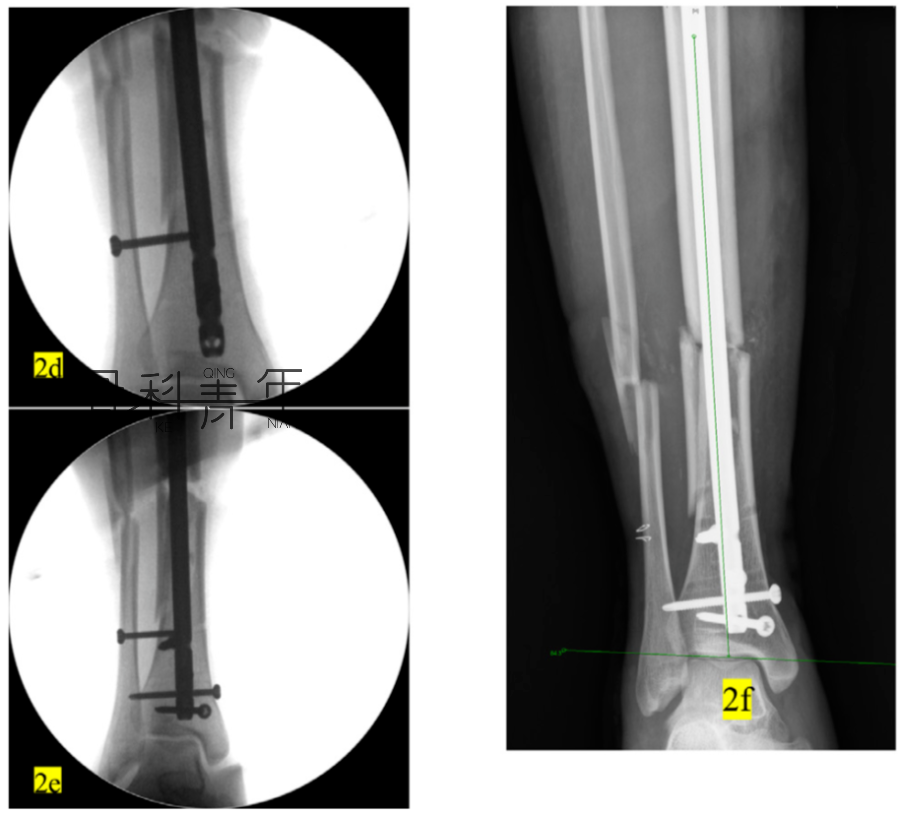

例2:

2a-2c:胫腓骨远端骨折,髓内钉固定,主钉插入及远端锁钉锁定后,可见骨折对线不良,存在移位。

2d-2f:依同法在移位平面拧入螺钉纠正移位,恢复对线后置入阻挡钉维持复位。